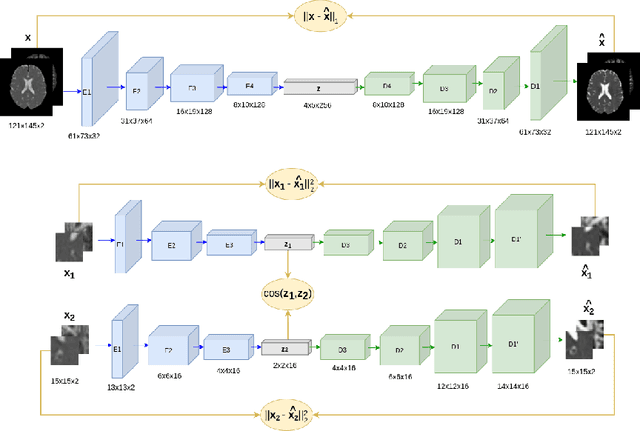

Although neural networks have proven very successful in a number of medical image analysis applications, their use remains difficult when targeting subtle tasks such as the identification of barely visible brain lesions, especially given the lack of annotated datasets. Good candidate approaches are patch-based unsupervised pipelines which have both the advantage to increase the number of input data and to capture local and fine anomaly patterns distributed in the image, while potential inconveniences are the loss of global structural information. We illustrate this trade-off on Parkinson's disease (PD) anomaly detection comparing the performance of two anomaly detection models based on a spatial auto-encoder (AE) and an adaptation of a patch-fed siamese auto-encoder (SAE). On average, the SAE model performs better, showing that patches may indeed be advantageous.